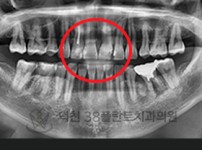

치료전후